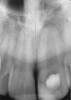

Clinical procedure: Regeneration of the endodontic pulp space is indicated for cases with very thin dentinal walls and an open apex that is more than 1 mm in diameter radiographically (Figure 4). Disinfection of the root canal system is performed using sodium hypochlorite irrigation followed by a triple antibiotic paste dressing that is left in place for 1 week. At the second visit, ethylenediaminetetraacetic acid (EDTA) is used to condition the dentin walls, which results in the release of growth factors, and bleeding is stimulated in the periapical tissues (where stem cells are located), with the aim of filling the pulp space with a stable blood clot, which would serve as the scaffold. MTA is then placed at the canal orifice in contact with the clot to protect it from coronal microleakage (Figure 5 and Figure 6). In time, the clot should be replaced with a reparative tissue of variable composition, and the root walls should continue to thicken due to the deposition of a dentin-like material on the pre-existing root dentin27,28 (Figure 7 and Figure 8).

Fig 4. Preoperative radiograph showing aggressive external root resorption and thin dentinal walls.

Figure 4